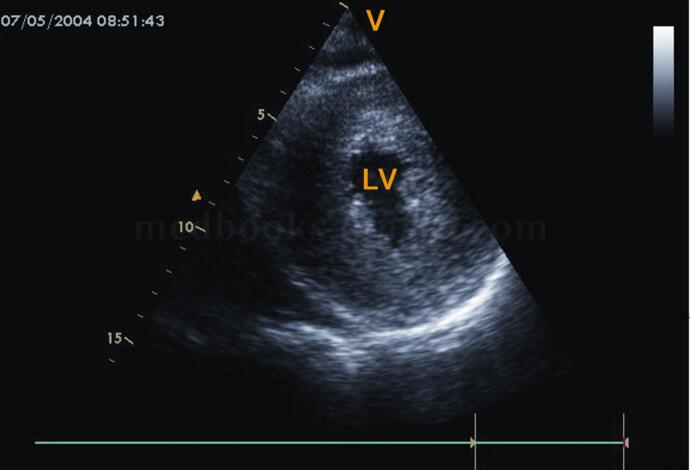

5)均匀肥厚型心肌病:各切面均可见各室壁明显均匀一致的增厚,回声增强,心腔明显变小(图2‐1‐202,图2‐1‐203),一般无左室流出道狭窄。

图2‐1‐202左室长轴切面室间隔与左室后壁对称性、均匀性增厚

图2‐1‐203 左室短轴切面左室壁对称性、均匀性增厚